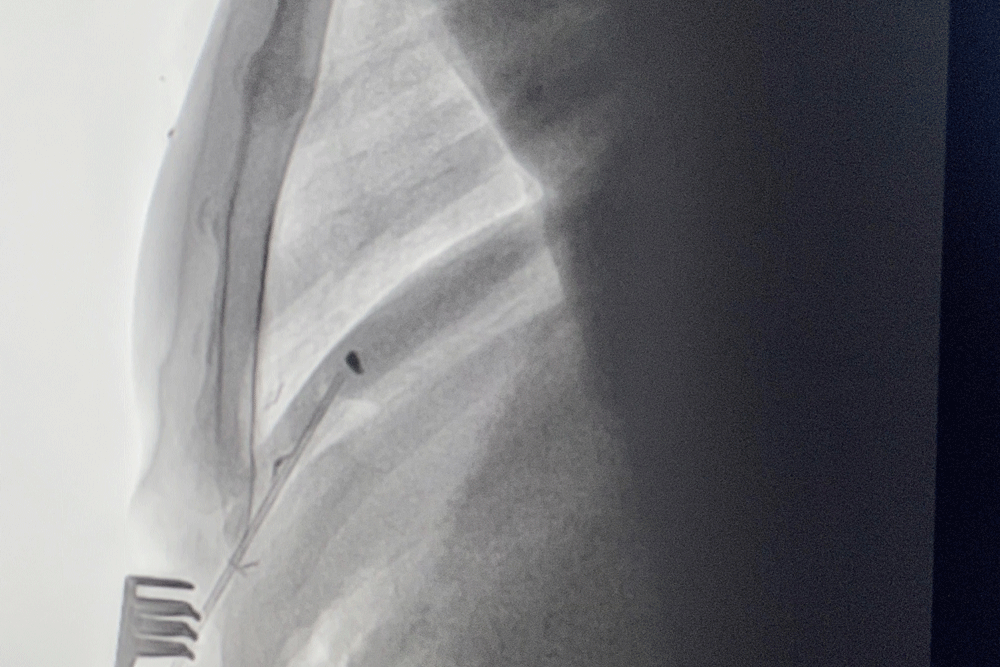

Здесь пациента обследовали и выяснили, что кусочек металла движется в такт сердечным сокращениям. Чтобы точнее определить местонахождение осколка, дважды сделали компьютерную томографию с 3D-реконструкцией. Оказалось, что инородное тело застряло в правом желудочке и может в любой момент закупорить лёгочную артерию. К тому же металлический предмет мог вызвать инфекцию.

Хирургическую процедуру провели в рентгеноперационной, где совсем недавно установили современный ангиограф, позволяющий видеть поражённую зону с точностью до доли миллиметра. Осколок извлекали из бьющегося сердца, с минимально возможным доступом.

В месте будущего разреза наложили круговой (кисетный) шов. Через небольшое отверстие хирург захватил и извлёк чужеродный объект и сразу же стянул края, чтобы не началось кровотечение.